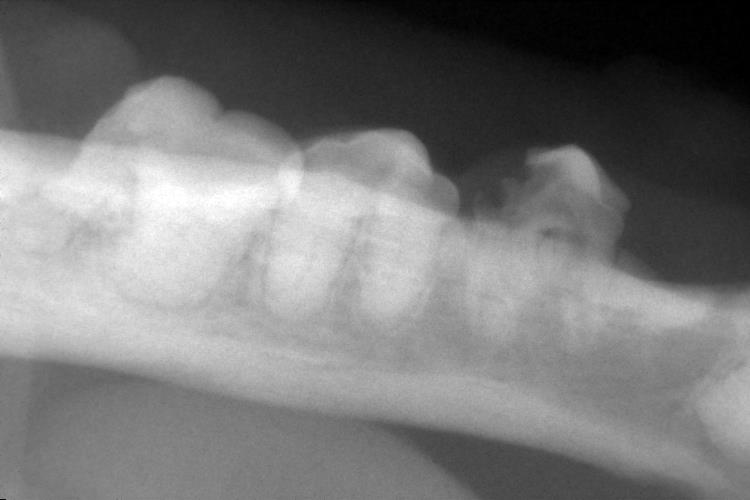

右下顎の臼歯のレントゲンです。

猫破歯細胞性吸収病巣(FORL)による吸収が確認されました。(〇印)

また、アンキローシス(骨性癒着)もみられました。(矢印)